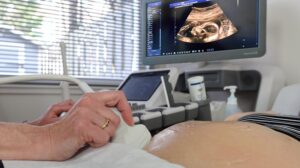

Je kunt bij ons als cliënt van Ella zes dagen in de week op drie verschillende locaties terecht voor het maken van medische echo’s.

Ella biedt je de volgende echo’s kosteloos aan:

Medische echo’s worden gemaakt om een medische reden. Je verzekeraar vergoedt deze: